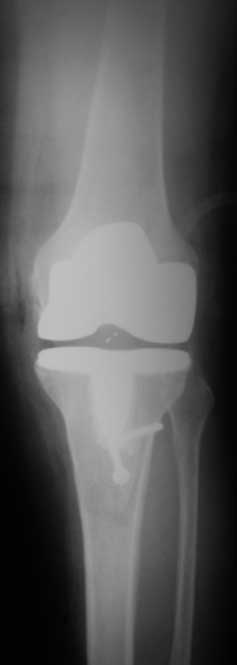

По данным R-грамм, хотя качество их не очень..., мне кажется имеется 2 основных ошибки: 1. высокий уровень остеотомии большеберцовой кости, при разгибетельных контрактурах его необходимо делать ниже.

2. Большой размер бедренного компонента. За счет этого переднезадний размер увеличен и ограничивает сгибание.

>1. высокий уровень остеотомии большеберцовой кости, при разгибетельных контрактурах его необходимо делать ниже.

уверяю вас, бедренный офсет не увеличен (снимок в ротации - ближайший п/о период, сложно вывести проекцию) экспериментируя с опилами к имеющимся проблемам можно было получить несбалансированное колено. Опил тибии стандартный на 10-ый вкладыш. Без рефиксированной бугристости колено было отлично сбалансировано, сгибание было до острого угла. проблема была именно в мягких тканях, конкретно в разгибательном аппарате, а не в опилах

снимки